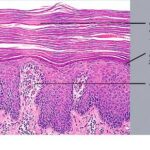

PATHOLOGY

Pathologic findings in pityriasis rubra pilaris vary according to the duration of the disease. The findings are most likely to be diagnostic in the acute phase, when hyperkeratosis, acanthosis with broad short rete ridges, and alternating orthokeratosis and parakeratosis oriented in both horizontal and vertical directions can be observed (see Pityriasis Rubra Pilaris At a Glance). Usually, there is a sparse superficial, perivascular lymphocytic infiltrate in the underlying dermis. Keratinous plugs of the follicular infundibula as well as perifollicular areas of parakeratosis may also be present. A prominent granular layer and dilated, but not tortuous, capillaries are features that help to distinguish pityriasis rubra pilaris from psoriasis, the most important differential diagnosis.